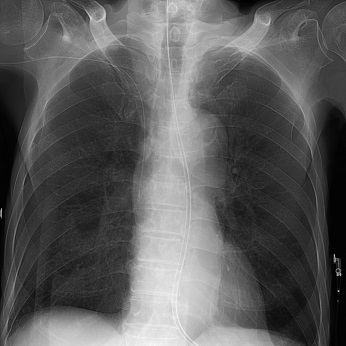

その他、中心静脈栄養カテーテル・ポートや人工透析用カテーテル挿入などさまざまな手技にも利用されています。